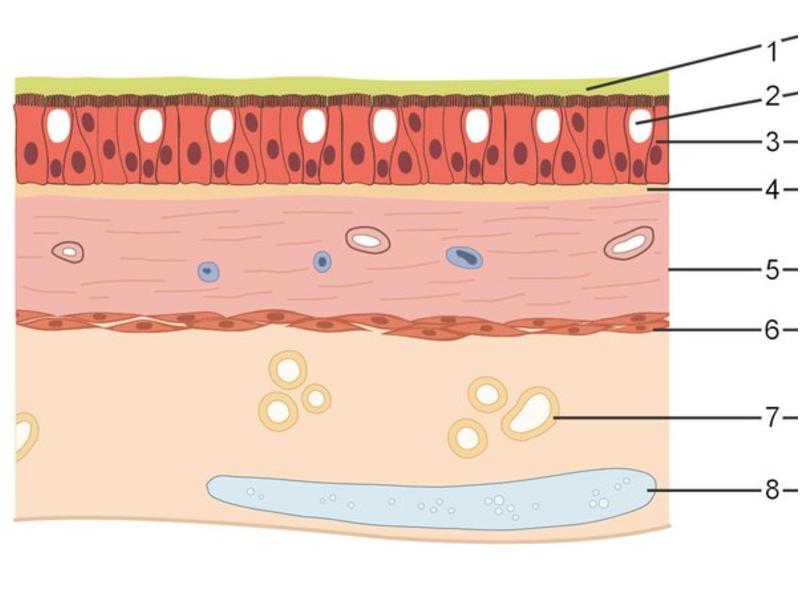

Trachea

Respiratory epithelium

- Pseudostratified

- Ciliated

- Columnar

- Epithelium with

- 4 Cells

- Ciliated columnar cells

- Non-ciliated columnar cells

- Goblet cells

- Basal cells